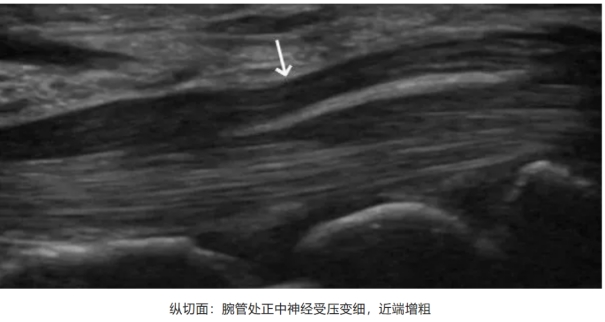

正常情况下,腕管内的正中神经在超声图像上应呈现为低回声的圆形或椭圆形结构。而当发生腕管综合征时,超声检查可发现正中神经在腕管狭窄处变扁,狭窄近端肿胀,患侧正中神经在腕管内明显增大,横截面积超过正常范围。